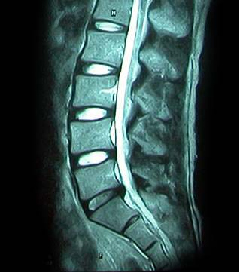

HLD on L-spine, Lt. L5 & S1 Radiculopathy

64세 여자환자는 2개월 전부터 요통과 다리 바깥쪽과 발등, 종아리 뒤쪽으로 저린 감각이 심해져서 개인병원에 들러 평가 및 물리치료를 받았으나 별다른 호전이 없고, 1주일 전부터는 허리를 숙이거나 물건을 들 때, 오래 걸을 때 통증이 더 심해져서 본원을 방문하였다. 12년전 집안일을 심하게 하고 난 후부터 간헐적인 요통을 발생하였으며, 별다른 치료 없이 지냈으며, 4년전 무거운 물건 들고 난 후 심하게 요통과 둔부의 통증까지 발생하여 MRI 촬영상 L1-2, L3-4-5, L5-S1 HNP와 Lt. L4 & both L5 nerve compression, Lt. S1 nerve compression 진단받고 Epidural steroid injection을 받고 통증 경감되었고, 간헐적으로 통증이 발생하였으나 별다른 치료 없이 헬스클럽에서 지속적인 운동으로 관리하였다.

• 척추 방사선 사진1